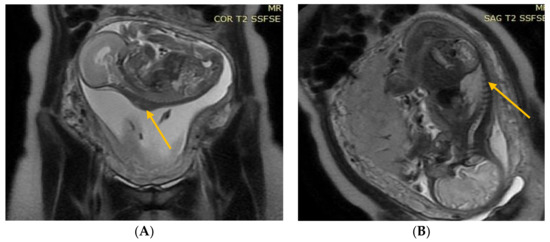

The results of the diagnostic MRI, performed between 21 and 24 weeks of gestation, were assessed (Figure 1 and Figure 2). During the test, the following parameters were evaluated: size and location of the spina bifida, presence and size of the hernia sack, size of the cerebral ventricles, structure of the posterior fossa, and severity of the Chiari malformation. Prenatal fetal NMR allowed to evaluate the development of the remaining fetal organs. Only fetuses with no other developmental defects were deemed eligible for the prenatal intervention. The NMR findings were compared to the perioperative imaging of the spinal split and hernia sack. After open fetal prenatal repair of spina bifida aperta, a follow-up ultrasound was performed at 2 weeks postoperatively, and repeated every 10–14 days. A follow-up fetal NMR was performed at 6–8 weeks postoperatively (Figure 1 and Figure 2).

Group II—84 (87.5%) patients with a hernia sack on diagnostic imaging and during surgical repair (Figure 2).

Figure 2. (A) Fetal NMR at 22 weeks of gestation. The arrow indicates the myelomeningocele. (B) Fetal NMR at 26 weeks of gestation (4 weeks after intrauterine myelomeningocele repair); the arrow indicates the site after a three-layer reconstruction of spina bifida aperta, with the area of contact between the repair site and the uterine wall.